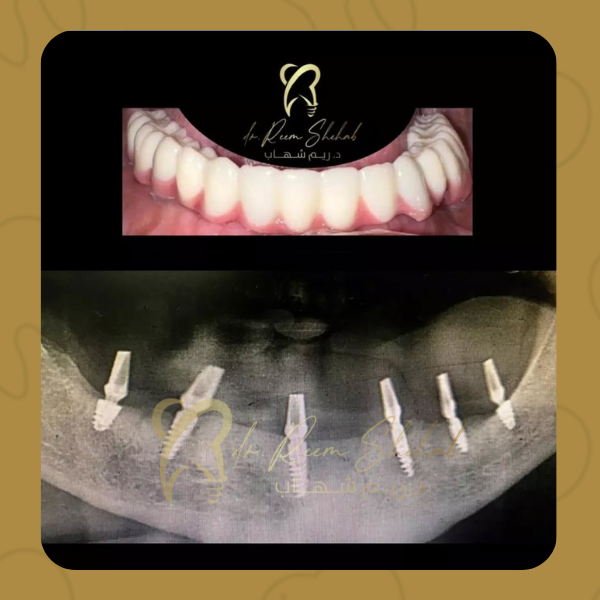

انا اليوم خلصت الحمدلله اشكر دكتورة ريم الشهاب على الزراعه ماشالله يدها خفيفه وحسن التعامل مع المريض وكيف تعطيك طاقه اجابيه وتخليكي مرتاحه وانتي عندها الله يسعدها يارب واشكر بعد الدكتور خالد على التعامل الراقي 🌷 …